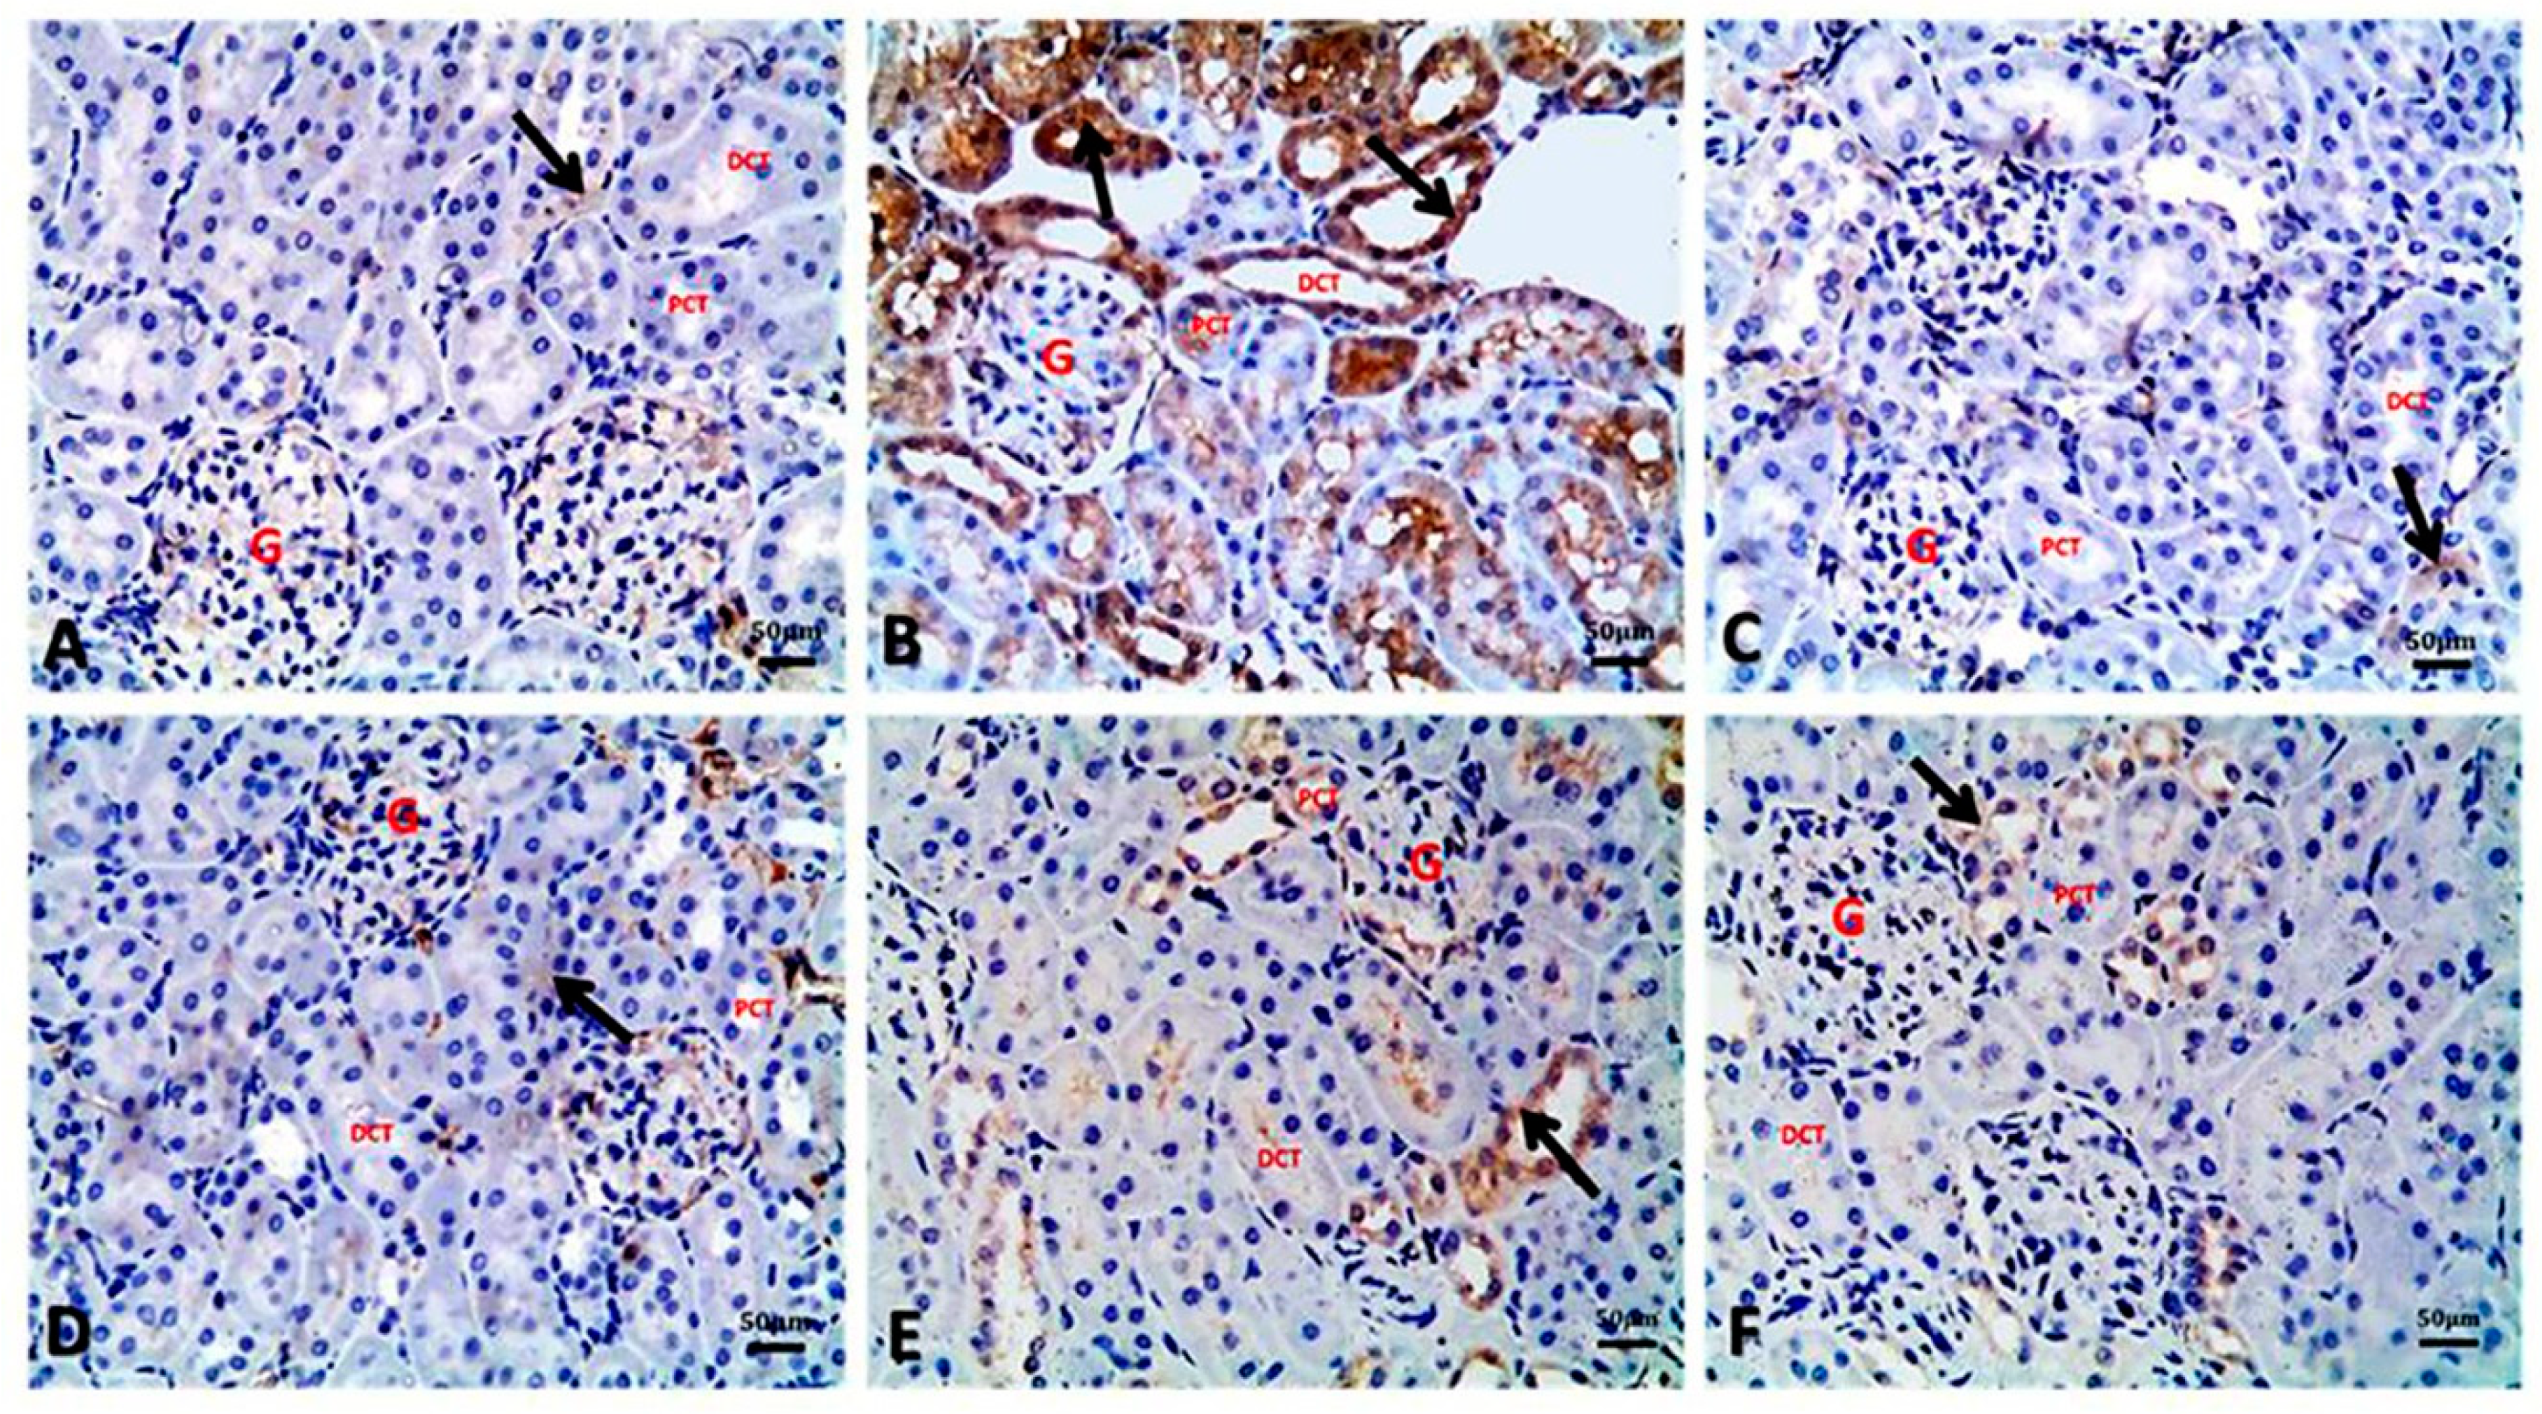

3.7. Argan Oil Modulated Betamethasone-Induced Increase of Bax and Caspase-3 and Decrease of Bcl-2 and PCNA Expressions in Renal Tissues of Rats